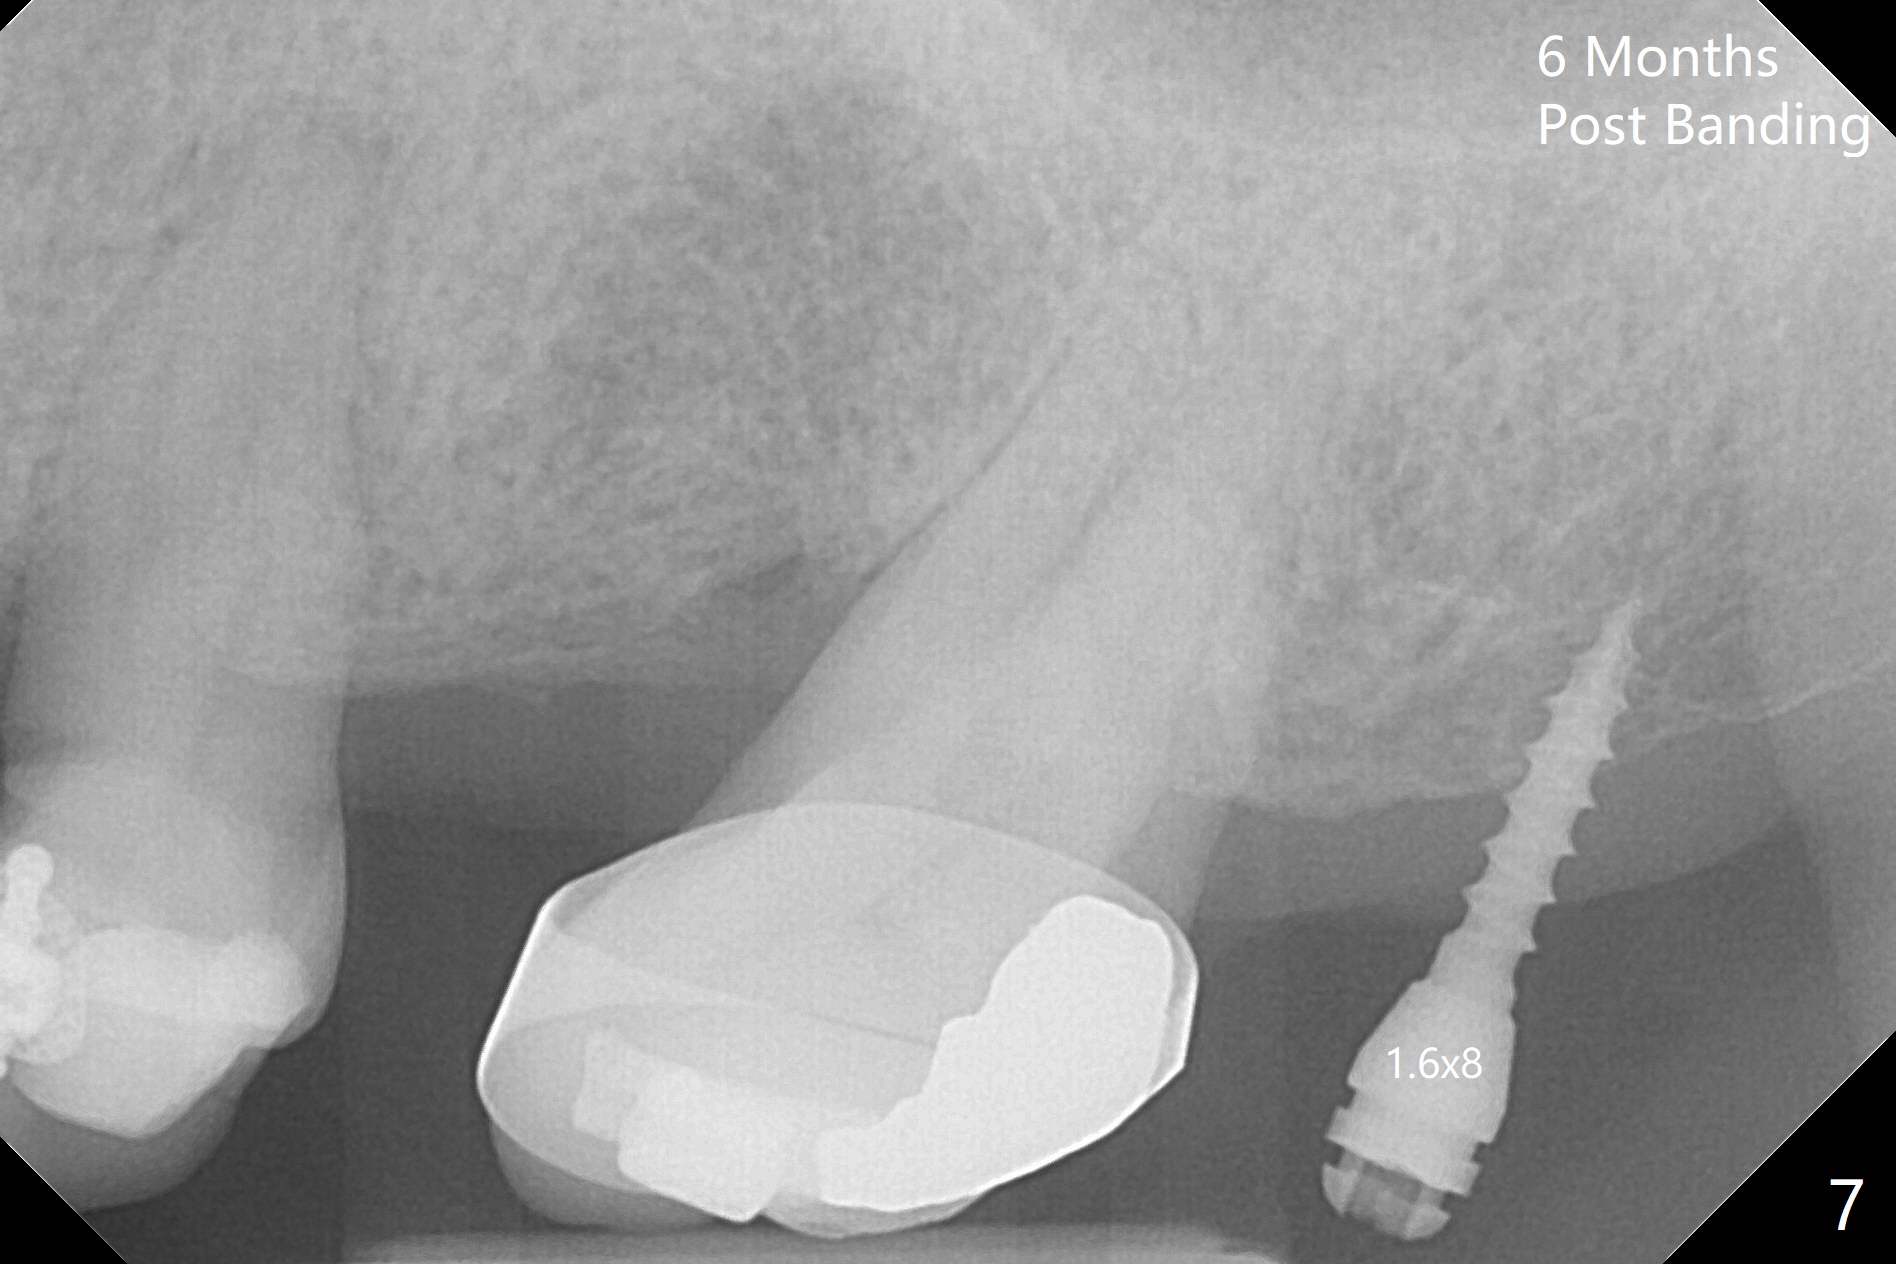

Ultradent Prime and Bond is used bracketing. The bonding system appears to be able to attach the brackets to porcelain crowns at #10 and 12 (Fig.3 (14 niti wire)). The 14 niti wire is not fully engaged (Fig.4). An open coil spring is used when the wire changes to 18 ss (Fig.5,6). Composite is placed to have clearance for UL7 to be distalized (Fig.5 *). To have the best anchor involving the implant at UL2, ligature wire is used between UL2-5 (Fig.6). In fact the anterior teeth are not good anchor. The bracket detaches from UL2 (implant) and UL5 keeps rotated, while UL7 is not distalized when open coil spring is placed between UL5-7. Nearly 6 months post banding, a 1.6x8 mm anchor pin is placed (Fig.7,8). Next visit the pin is loose and replaced with a ball type 1-piece implant (2x10(2) mm). Although the latter remains apparently stable, UL7 appears to remain in place. It seems necessary to place a restorative implant at UL6 as a future anchor (Fig.9: 3.5x11.5 mm).